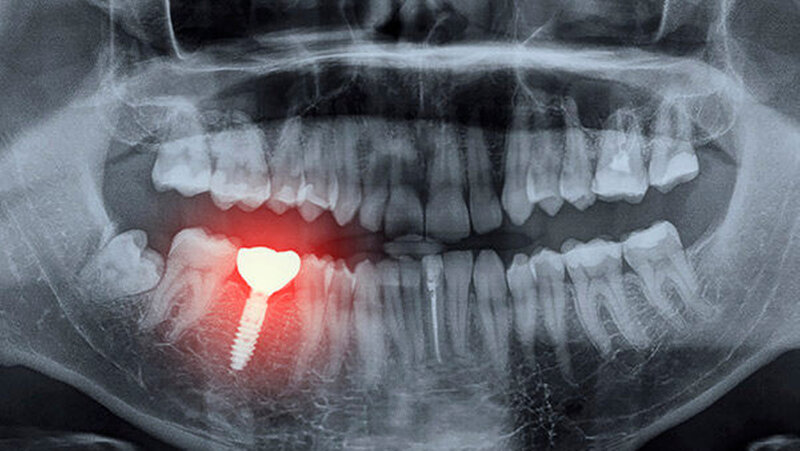

Antidepressiva und Implantatverlust

Während des Untersuchungszeitraums erhielten 5.456 Patienten ihr erstes Implantat (Durchschnittsalter 53 Jahre). Die mediane Follow-up-Dauer betrug 5,3 Jahre (Interquartilbereich: 2,3 bis 10,2 Jahre). Bei 4.927 Patienten kam es nicht zu einem Implantatversagen. Dem gegenüber ermittelten die WissenschaftlerInnen 529 Patienten mit Implantatversagen.

In der Gruppe der Patienten mit dem SSRI Sertraline in der Vorgeschichte war ein erhöhtes Risiko für Implantatversagen feststellbar. Das Risiko, das Implantat zu verlieren, lag in dieser Population um 60 Prozent höher. Die Einnahme von SSRI zum Zeitpunkt der Implantation oder eine SSRI-Anwendung nach der Implantion waren nicht in signifikantem Maße mit einem erhöhten Risiko für Implantatversagen verbunden.

Diese Ergebnisse deuten darauf hin, dass eine Langzeitmedikation mit SSRI die Knochenheilung während der kritischen Phase der Heilung der Knochenimplantat-Grenzfläche negativ beeinflusst. Weiterin legen die Ergebnisse nahe, dass die Einnahme mehrerer SSRI das Risiko eines Implantatversagens signifikant erhöht. Im Vergleich zu Patienten ohne SSRI-Anamnese hatten jene, die zwei oder mehr SSRI verwendeten, ein signifikant höheres Risiko das Implantat zu verlieren.